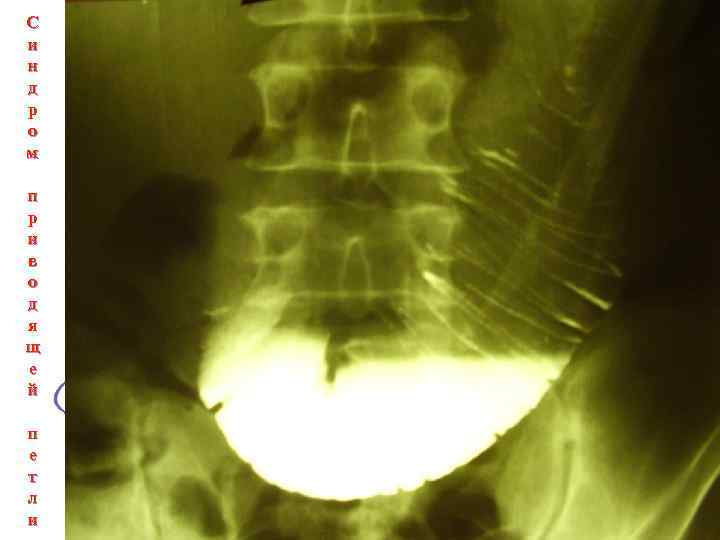

Синдром приводящей петли Rg-признаки: при синдроме приводящей петли наблюдаются забрасывание и длительная задержка (стаз) взвеси бария в переполненной жидким содержимым приводящей петле тощей кишки, расширение просвета и отек слизистой оболочки. При этом складки слизистой оболочки утолщены, ригидны, контуры кишки фестончаты. Пальпация ее болезненна. Переход содержимого в отводящую петлю затруднен

Синдром приводящей петли Рентгенография при синдроме приводящей кишки

С и н д р о м п р и в о д я щ е й п е т л и